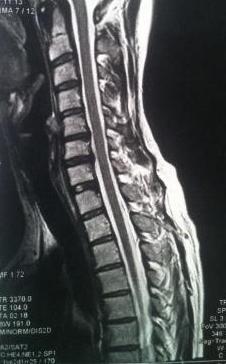

Der Vollständigkeit halber das MRT von HWS und oberer BWS:

MRT HWS BWS Forumgröße.jpg

MRT HWS BWS Forumgröße.jpg (22.42 KiB) 20989 mal betrachtet

Gruß, Gaby